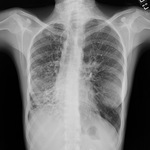

Radiografía de tórax que muestra una adenopatía hiliar bilateral en un paciente con sarcoidosis

De la colección personal del Dr. M.P. Muthiah, Departamento de Medicina Intensiva y Pulmonar y Medicina del Sueño, University of Tennessee